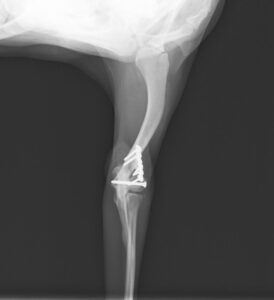

階段からころげおちてかかりつけ医を受診し、X線にて左側「上腕骨外顆骨折」を認めたため、当院の整形外科にご紹介いただきました。この症例は、尺骨の骨切り術を併用し外顆の骨折部分を整復しています。術後の経過は良好で、手術から7ヶ月後に尺骨のインプラントを除去し、治療終了としました。